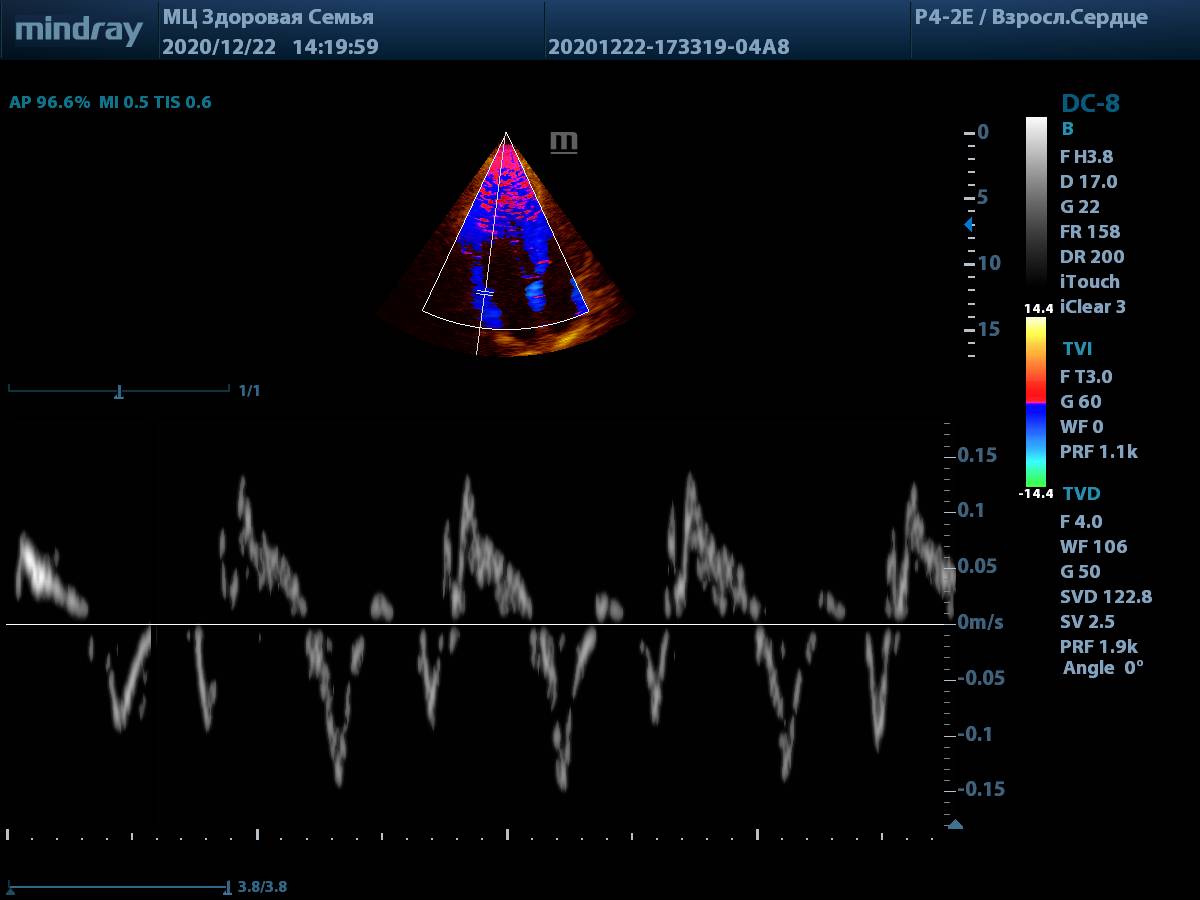

3. Тканевая допплерография (TDI). Всё просто и удобно, достаточно нажать одну кнопку. Цветовая карта по умолчанию яркая, не нужно настраивать её усиление для выбора точки установки контрольного объема.